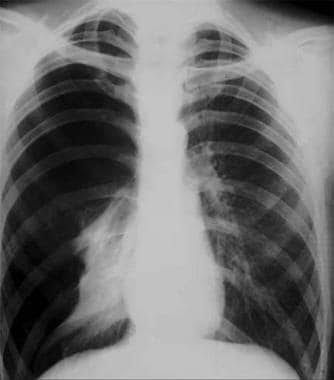

Investigations for pneumothorax

A pneumothorax is generally diagnosed using a chest X-ray. In some cases, a computerized tomography (CT) scan may be needed to provide more-detailed images. Ultrasound imaging also may be used to identify a pneumothorax.